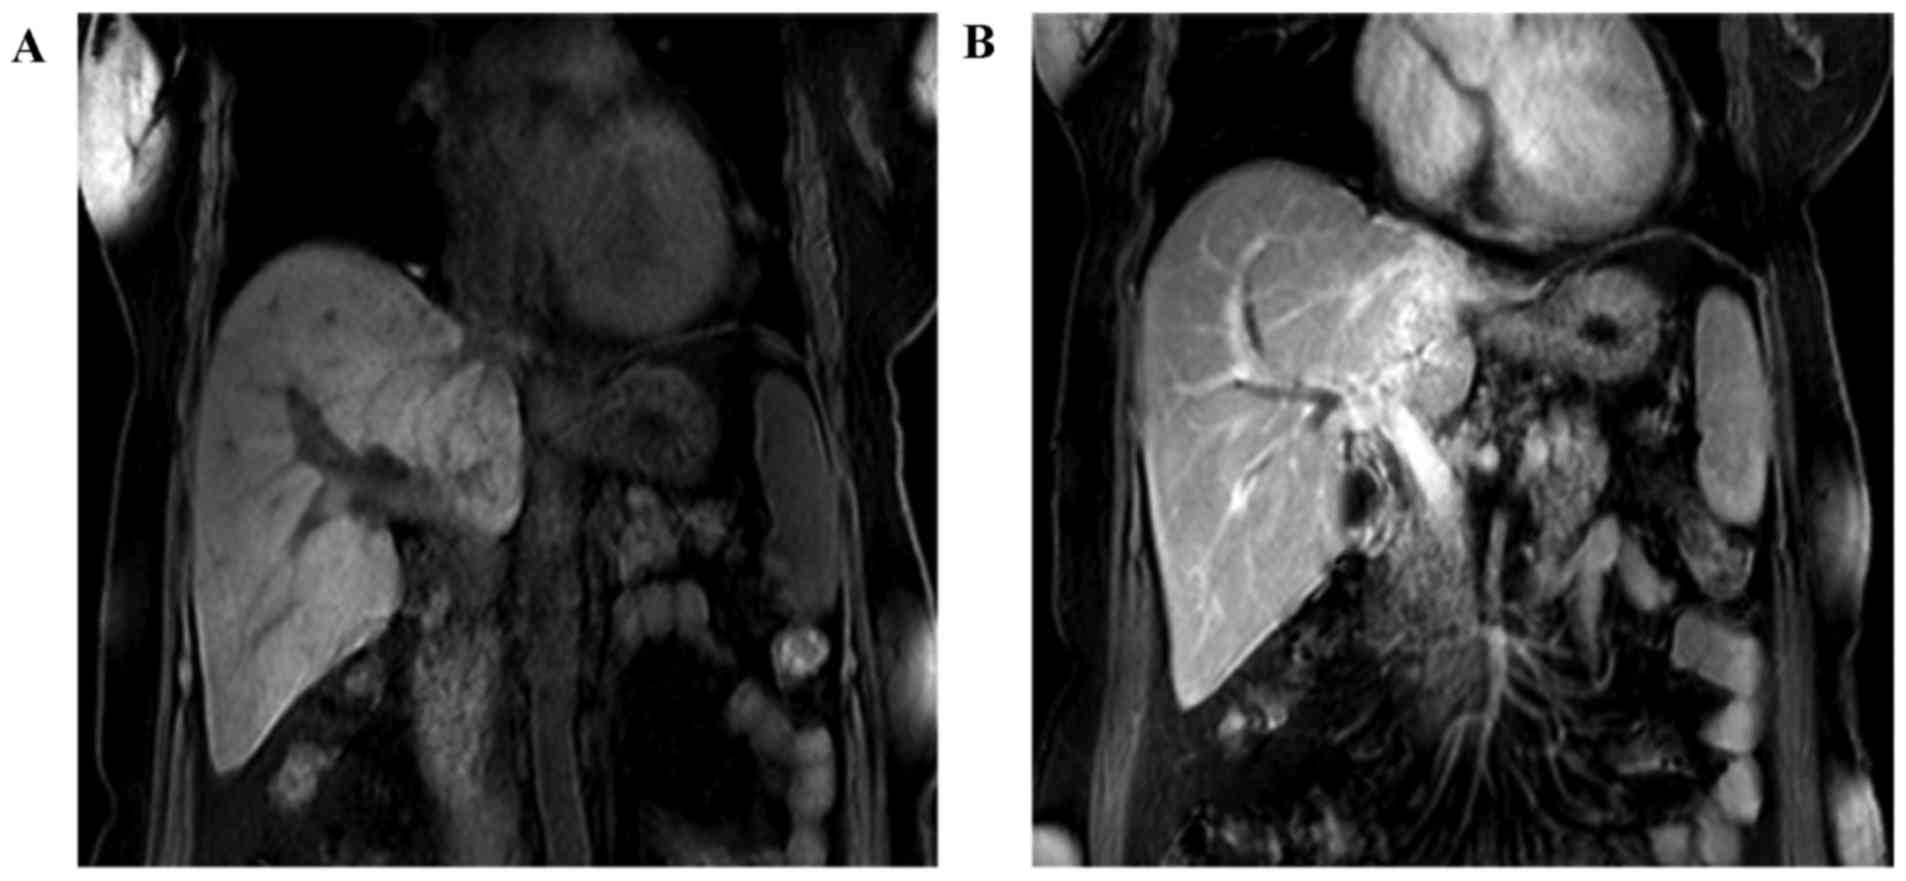

A 63-year-old female patient with a 2 weeks' history of intermittent epigastric pain was admitted to the Sun Yat-sen Memorial Hospital, Sun Yat-sen University, Guangzhou, China. A physical examination did not reveal any neurological symptoms, and the patient denied having any associated medical history. An magnetic resonance imaging (MRI) scan of the abdomen revealed that the left bile duct was replaced with a mass, and the intrahepatic biliary duct was dilated; furthermore, the left branch of the portal vein had been invaded (Fig. 1). Simultaneously, a laboratory examination revealed a level of the tumor marker, carcinoembryonic antigen (CEA), of 6.3 ng/ml (normal value, ≤5 ng/ml), and a cancer antigen 19-9 (CA19-9) concentration of 316 U/ml, as well as a moderately increased concentration of serum total bilirubin.

Figure 1.

Results of the MRI examination of the abdomen. (A and B) The left branch of portal vein was invaded. MRI, magnetic resonance scanning. CT, computed tomography.